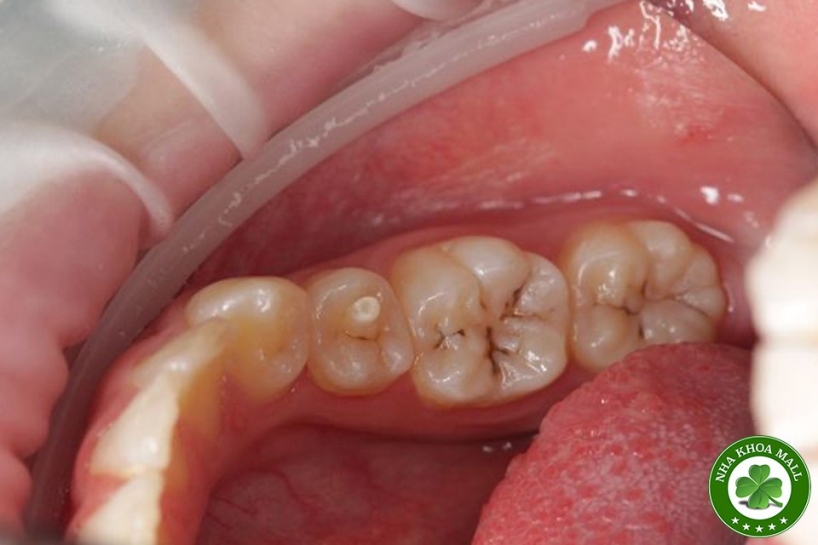

Núm phụ mặt nhai là một bất thường phát triển răng, thuộc nhóm Dens evaginatus, biểu hiện bằng một múi dư nhô lên ở mặt nhai, thường gặp nhất ở răng tiền cối hàm dưới (Leong’s premolar). Về mặt mô học, núm phụ này có thể chứa: Men, Ngà Và đặc biệt: một phần mô tủy kéo dài vào trong núm. Chính yếu tố này khiến núm phụ mặt nhai trở thành nguy cơ cao gây biến chứng nội nha, đặc biệt ở bệnh nhân trẻ.

Chủ yếu ở răng tiền cối hàm dưới

Dễ gãy hoặc mòn núm phụ → lộ tủy

Tạo điểm chạm sớm → sang chấn khớp cắn